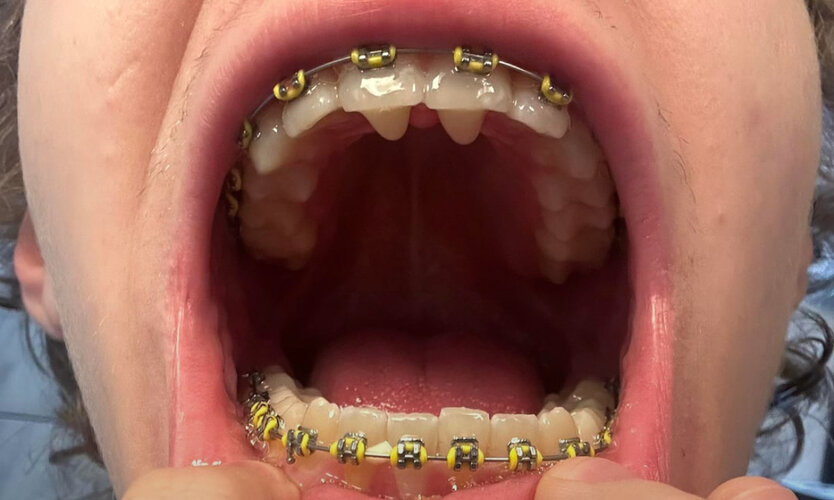

$27K Custom 8 TAD FME Pro finally installed on my guy Brandon

from Dr. Jaffari ofc

Best expander on the market currently.

"Waiting for the professional pics + CBCTs from Dr Jaffari, but just had the 8 TAD FME Pro finally installed. Wasn’t too painful, feeling a lot of pressure on my maxilla rn tho. 1 turn a day for now until I split, aiming for ~8mm expansion. Expecting trimax in about 11 months as long as I split quickly"

Pure controlled palatal expansion with significant midface expansion.